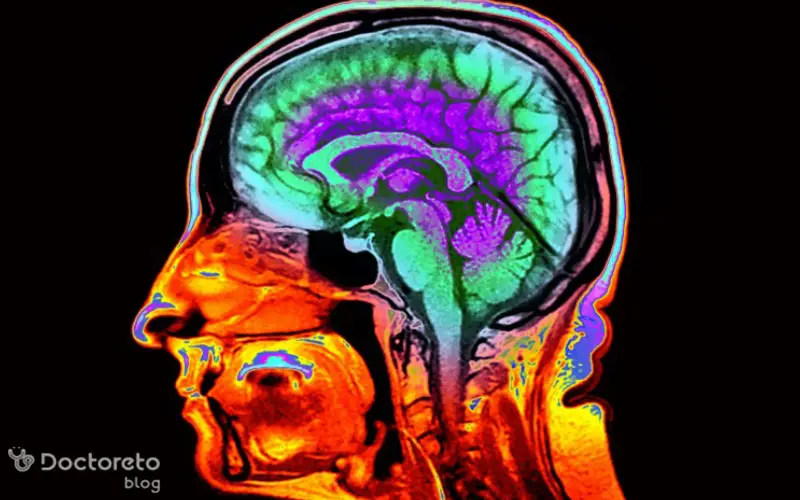

نوار مغز یا EEG یکی از ابزارهای مهم پزشکی برای بررسی فعالیتهای الکتریکی مغز است. این روش به ویژه در کودکان اهمیت بالایی دارد، زیرا مغز کودک در حال رشد و تغییرات سریع است و برخی مشکلات عصبی ممکن است در مراحل اولیه قابل شناسایی باشند. نوار مغز کودکان اطلاعات دقیقی درباره عملکرد مغز ارائه میدهد و میتواند به پزشکان در تشخیص و مدیریت اختلالات مختلف کمک کند. در این مقاله از دکترتو با شما هستیم تا به طور مفصل به موضوع نوار مغز کودکان بپردازیم.

نوار مغز کودکان همانند بزرگسالان فعالیتهای الکتریکی مغز را ثبت میکند، اما ویژگیها و الگوهای آن در کودکان متفاوت است. مغز کودک در حال رشد است و الگوهای امواج مغزی به مرور زمان تغییر میکنند، بنابراین تفسیر نوار مغز کودک نیازمند تجربه و دانش تخصصی است. نوار مغز کودکان از طریق قرار دادن الکترودهای کوچک روی پوست سر انجام میشود. این الکترودها امواج الکتریکی مغز را دریافت کرده و آنها را به شکل نمودارهایی قابل تحلیل برای پزشک ارائه میکنند.

این نمودارها شامل امواج با فرکانسها و دامنههای مختلف هستند که هر کدام اطلاعات خاصی درباره عملکرد مغز ارائه میدهند. هدف اصلی از انجام نوار مغز کودکان، بررسی عملکرد مغز و شناسایی هرگونه ناهنجاری یا اختلال احتمالی است. این بررسی میتواند به تشخیص زودهنگام مشکلات عصبی کمک کند و روند درمان و مراقبت از کودک را تسهیل کند.